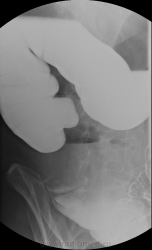

Пациентка 70 лет, направлена на ирригоскопию для исключения органической патологии, предворительно дважды проходила колоноскопию(без патологии), последний раз на кануне проведения исследования.

Снимки восходящий отдела ободочной кишки сделаны в положении на животе и стоя. Ваше мнение?

Последний и предпоследний снимок это восходящий отдел ободочной кишки, а если была бы перистальтика то мы бы увидели на последнем снимке в вертикальном положении законтрастированную слепую кишку.

Да, я предпологаю об инфильтративной форме рака. Эндоскописты только со второго раза так же описали о сужении просвета на 4/5, взяли биоптат, думаю на этой неделе готова будет.

Прекрасная подготовка пациентки к исследованию, мастерское владение методикой первичного двойного контрастирования и как следствие результат.Похоже на рак толстой кишки.

Результат гистологии-аденокарцинома.

Данный снимок сделан на животе Игорь Иванович, отмеченный Вами участок это ещё восходящий отдел, далее я отметил красными стрелками где частично контраст прошол в н/3 восходящего отдела и слепую кишку . поэтому диагноз звучит как рак восходящего отдела ободочной кишки.